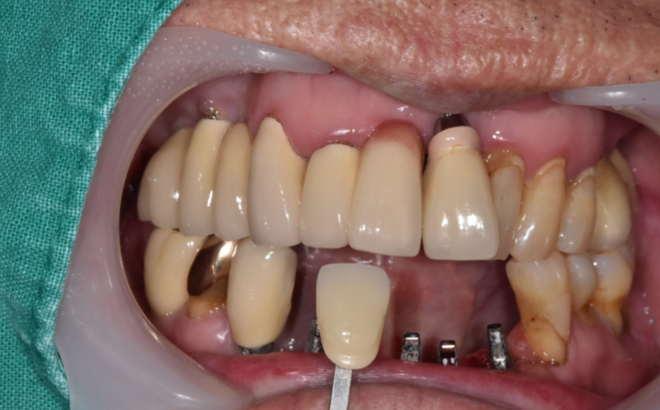

환자분의 요청대로 육안 검사를 시행

보철이 한지 오래되어 뿌리가 노출되고

손으로만 건드려도 흔들거리는 상황

230725

수술 한 달 뒤 사진입니다.

앞니는 무엇보다도 중요한 것이 예.뻐.야 합니다.

임시치아를 만들어드렸습니다.

231120

강동구 치과 앞니 임플란트 완성 사진입니다.

실제 보철물을 보실까요~?

옆에 치아와 색깔이 잘 맞게 나왔습니다.